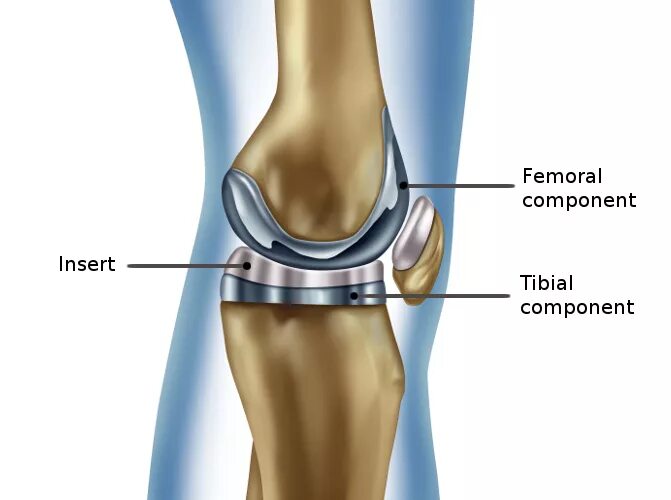

Протезирование суставов по квоте